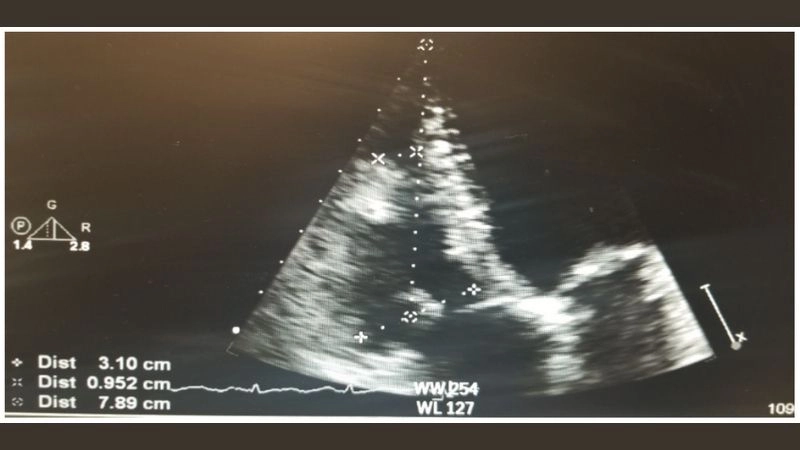

Rhabdomyoma is a rare benign tumor of striated muscle, commonly affecting the heart in children. Images often highlight cardiac masses that disrupt heart rhythm and function.

Precise image for rhabdomyoma diagnosis clarity